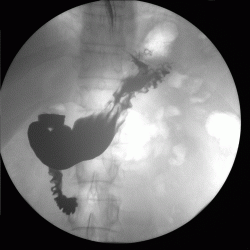

пациента беспокоят боли в области эпигастрия.Выполнена ФГДС вот результат. Пищевод свободно проходим с нормальным просветом и слизистой. Розетка кардии эластиная, смыкается не полностью. В желудке умеренное количество жидкости и слизи с примесью желчи. Слизистая оболочка розовая, отечна, складки нормальной ориентации, утолщены, извиты, эластичность стенок желудка и перистальтика сохранены во всех отделах. В ср/3 тела желудка, на задней стенке определяется язвенный дефект 1,5*0,8 см округлой формы, с припднятыми отечными краями, с конвергенцией складок слизистой, в дне фибрин. Окружающая слизистая отечна, разрыхлена,застойна. При щипковой биопсии подслиистый слой плотный. Антральный отдел, привртаник, луковица и постбульбарный отдел ДПК без особенностей.

ЗАКЛЮЧЕНИЕ: Гипертрофический гастрит. Язва ср/3 тела желудка, maligna ?

Взяли биопсию : покровно-ямочный эпителий без атипии.

Назначено лечение. Контрольная ФГДС- положительная динамика . Размеры язвы 1х0,7 см.

Ну и на последок дообследован рентгенскопически.

По поводу самого обследования. Контраст в нашей клинике- "Бар Випс", ну а газообразующая смесь, как обычно , сода+лимонная кислота.

А сама методика как везде. Исследование выполнено на аппарате США фирмы"general electric" presicion.

Уважаемая Людмила Александровна! Классика жанра! Все рентгенологические симптомы язвы желудка налицо!